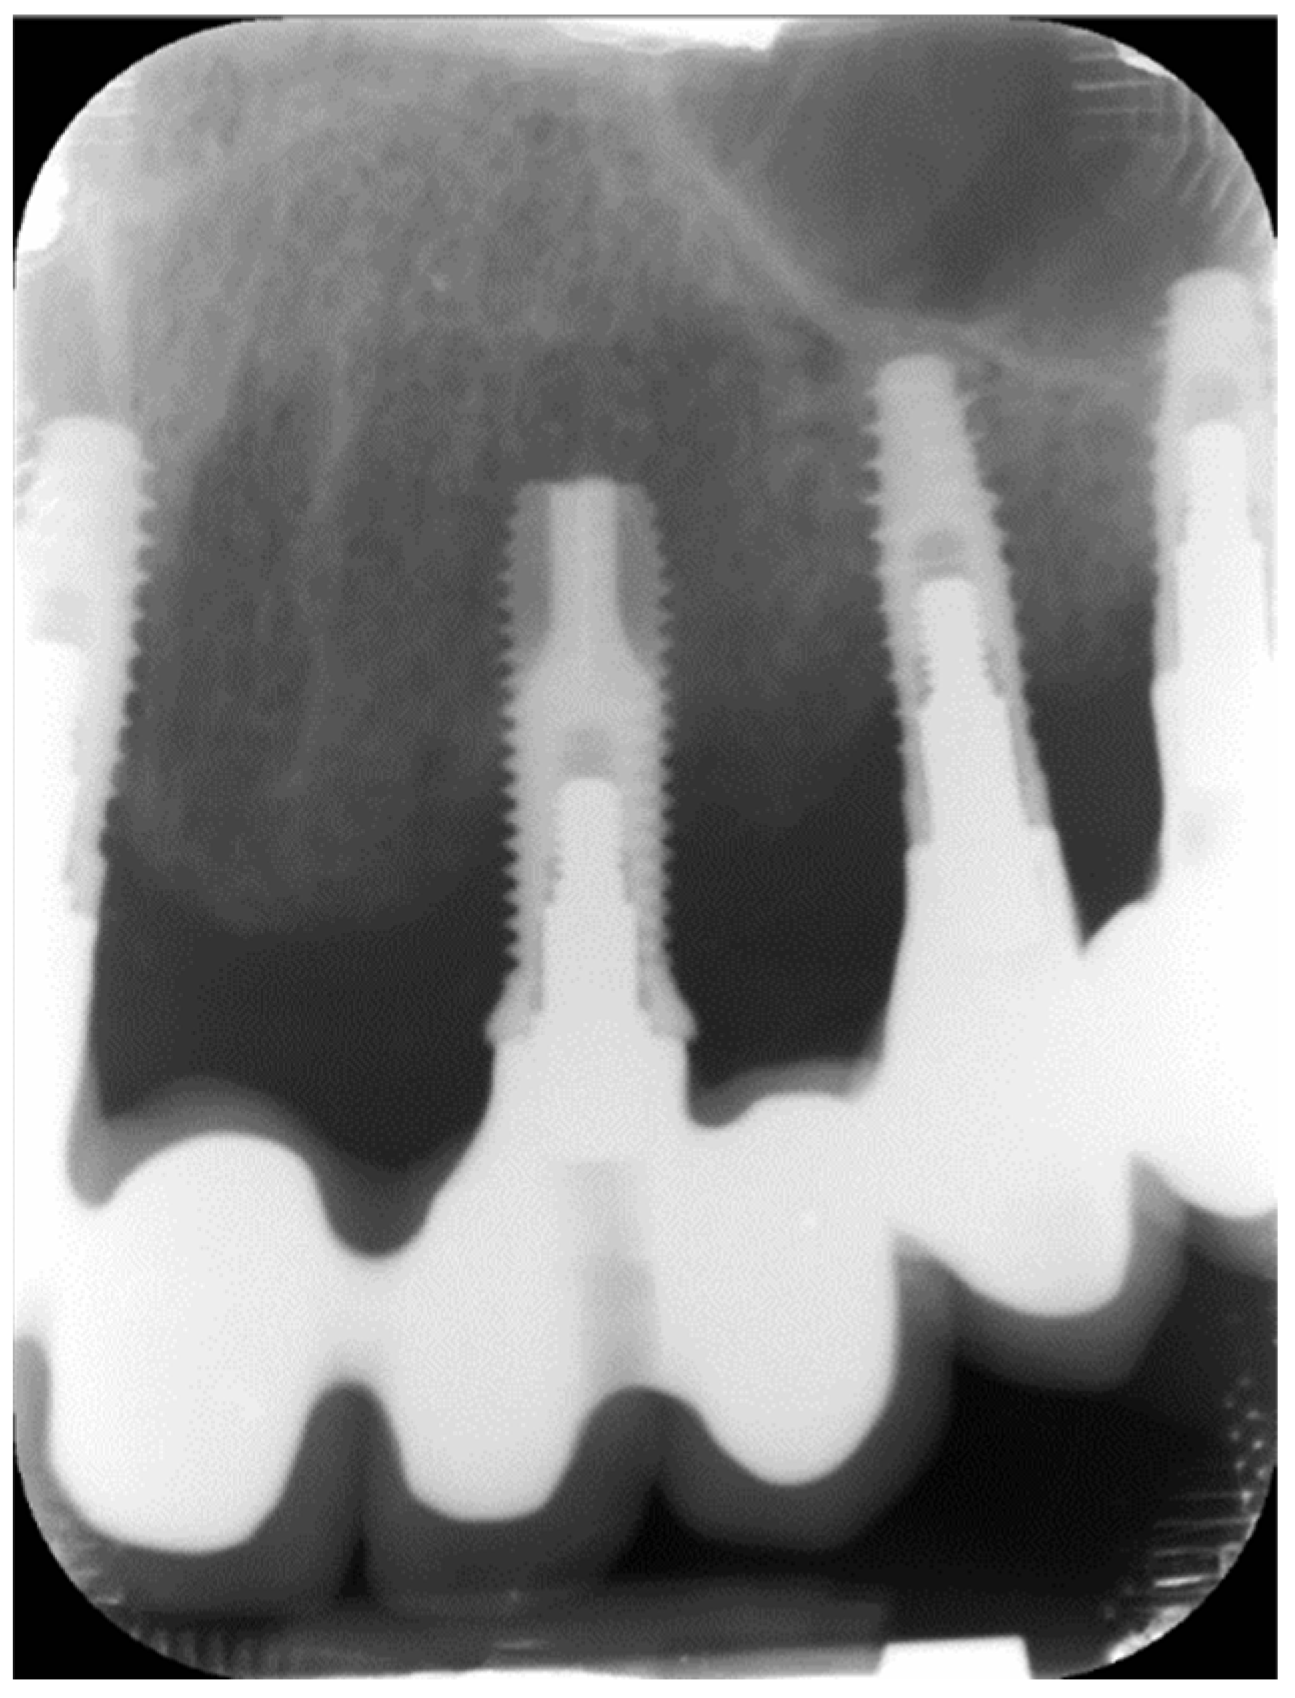

Variables related to the subject were collected; such as age, gender, tobacco consumption and history of periodontitis, as well as variables related to the implants. The main parameter was the presence of keratinized mucosa (KM), as well as the width of KM measured in millimeters in the mid-buccal surface of the implants with a periodontal probe CP 15 from Hu-friedy® (Frankfurt, Germany). The absence of KM was considered when there was non-keratinized mucosa at the gingival margin of the implant (Figure 1). Recession (the apical migration of the gingival margin) was measured in the mid-buccal surface from the cervical margin of the crown, where the gingival margin was located at the time of prosthesis placement. Other parameters were: Silness and Löe plaque index (Figure 2); probing depth using a plastic periodontal probe (Premier®) (at six points: mesiobuccal, buccal, distobuccal, mesiopalatal, palatal and distopalatal) (Figure 3); bleeding (its presence or absence was measured); suppuration (its presence or absence was measured); and bone level (distance, in mm, between the implant shoulder and the base of the defect) using Rhinoceros® software (Robert Mcneel & Associates, Seattle, WA, USA) on the parallelized radiographs. Bone loss due to peri-implantitis was considered when a crater-shaped image was observed surrounding the implant (taking as reference the most apical area of the crater) (Figure 4), accompanied by clinical signs such as bleeding or suppuration. The years since prosthesis placement were also noted. All data were collected by a single operator who visually analyzed the esthetics of the peri-implant tissues.

Figure 4.

Bone loss.

The mean bone loss was 2.2 ± 2.3 mm, ranging from 0 to 9.9 mm and it was significantly higher in patients with peri-implantitis (3.8 ± 2.1 mm), since the reduced bone loss in healthy implants (0.5 ± 0.6 mm) was attributed to the physiological remodeling produced after implant loading. Interestingly, there was a 1.6 mm mean difference in bone loss in implants with KM (3.1 mm) and without KM (4.7 mm), reaching a statistical significance (p < 0.001). Implants without KM had lost more bone.